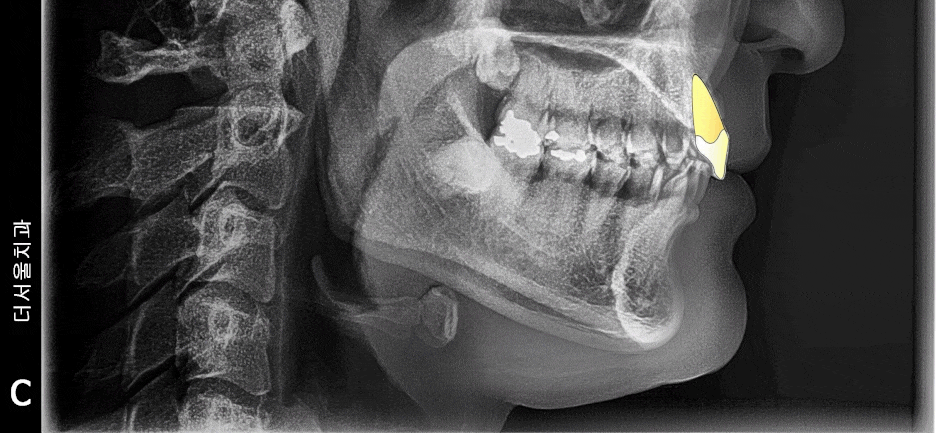

앞서 보여드린 사진에서,

두부 방사선 측면 사진(Ceph) 이 있었죠?

거기에 가상의 지표를 찍게 됩니다.

cephalometric bony landmark 라 부르는데,

사진으로 보여드리겠습니다.

이렇게, 해부학적 요소에 따라서

랜드마크를 찍어서 발치를 해야 되는지

브라켓은 어디에 붙여야 되는지 등을

알 수 있습니다.

저는 여기서, 코 끝과 턱 끝을 이은

‘심미선’ 이라 부르는 리케츠 라인을 주로 봅니다.

이 선을 기준으로, 입술이 튀어나와있다면

‘돌출입’ 그렇지 않다면 ‘정상’ 의 범주로 보며

발치 결정의 기준점이 될 때도 있습니다.